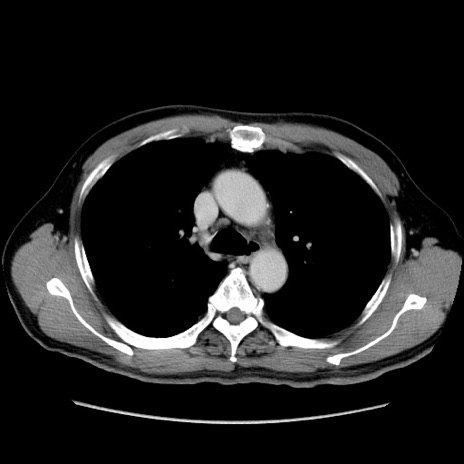

【症例】60歳代 男性

【主訴】右鼠径部膨隆

【現病歴】1年程前より右鼠径部膨隆あり。自己にて還納可能だったため放置していた。3時間前より右鼠径部の脱出を認め、還納困難となり受診。

【身体所見】右鼠径部に小児頭大の膨隆あり。弾性硬であり、用手還納は困難。左鼠径部にも膨隆を認める。脱出はなし。